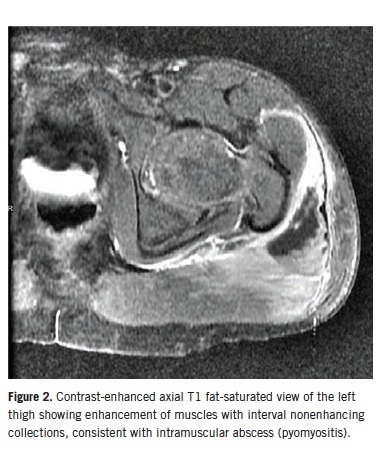

An ultrasonogram of the hip showed edema around the hip joint but no effusion. Magnetic resonance imaging (MRI) revealed findings consistent with extensive myositis involving multiple left hip muscles, as well as pyomyositis with associated intramuscular abscesses involving the left gluteus maximus muscle (Figures 1 and 2). There was no evidence of septic arthritis or osteomyelitis. The patient was started on a regimen of intravenous clindamycin and vancomycin.